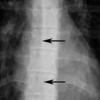

paraspinal lines